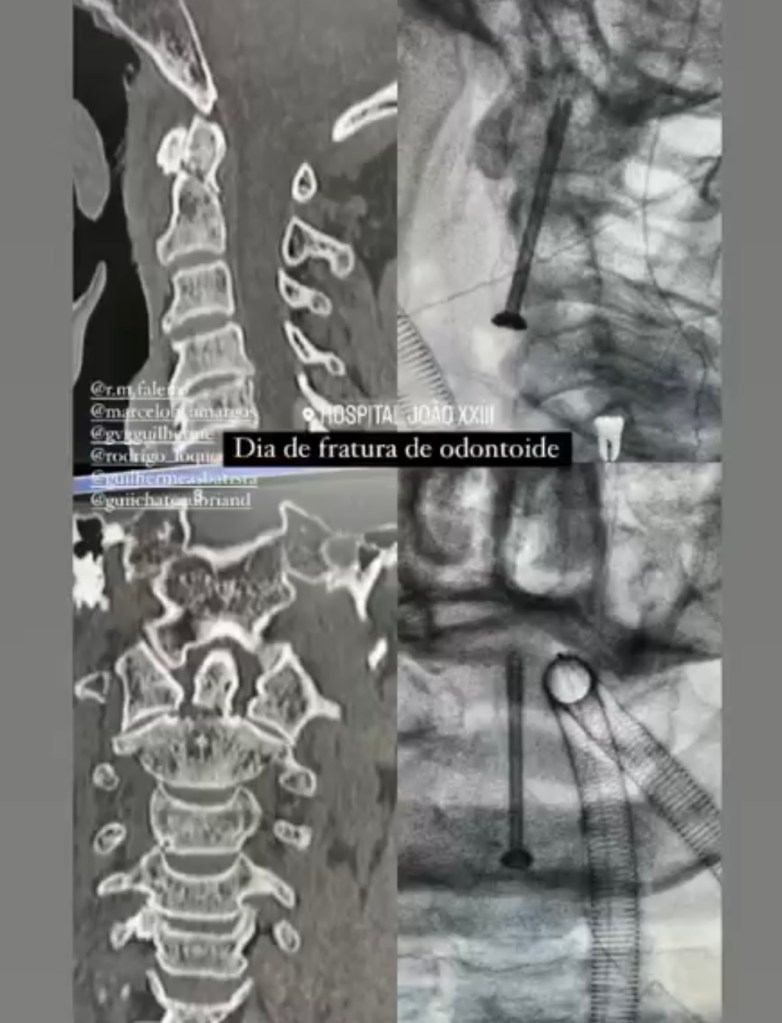

GALERIA De cirurgias

Abaixo você pode conferir imagens de algumas cirurgias já realizadas por Dr. Marcelo Camargos. Caso tenha alguma dúvida ou interesse, não deixe de fazer contato para maiores esclarecimentos!